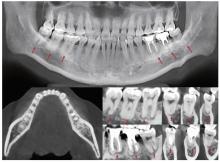

Figure 2

CBCT images of the patient at initial presentation Three radiographic stages of COD concurrently shown in multifocal lesions across six mandibular molars: osteolytic stage (38/46/48), cementoblastic stage (36/37), mature stage (47). The red arrow indicates the COD lesion. COD, cemento-osseous dysplasia; CBCT, cone beam computed tomographic."